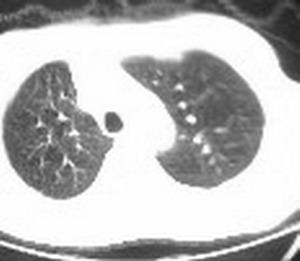

标题: CT6943:[讨论]胸部,M/67Y,体检发现。

ct值约12hu。

ct值约12hu